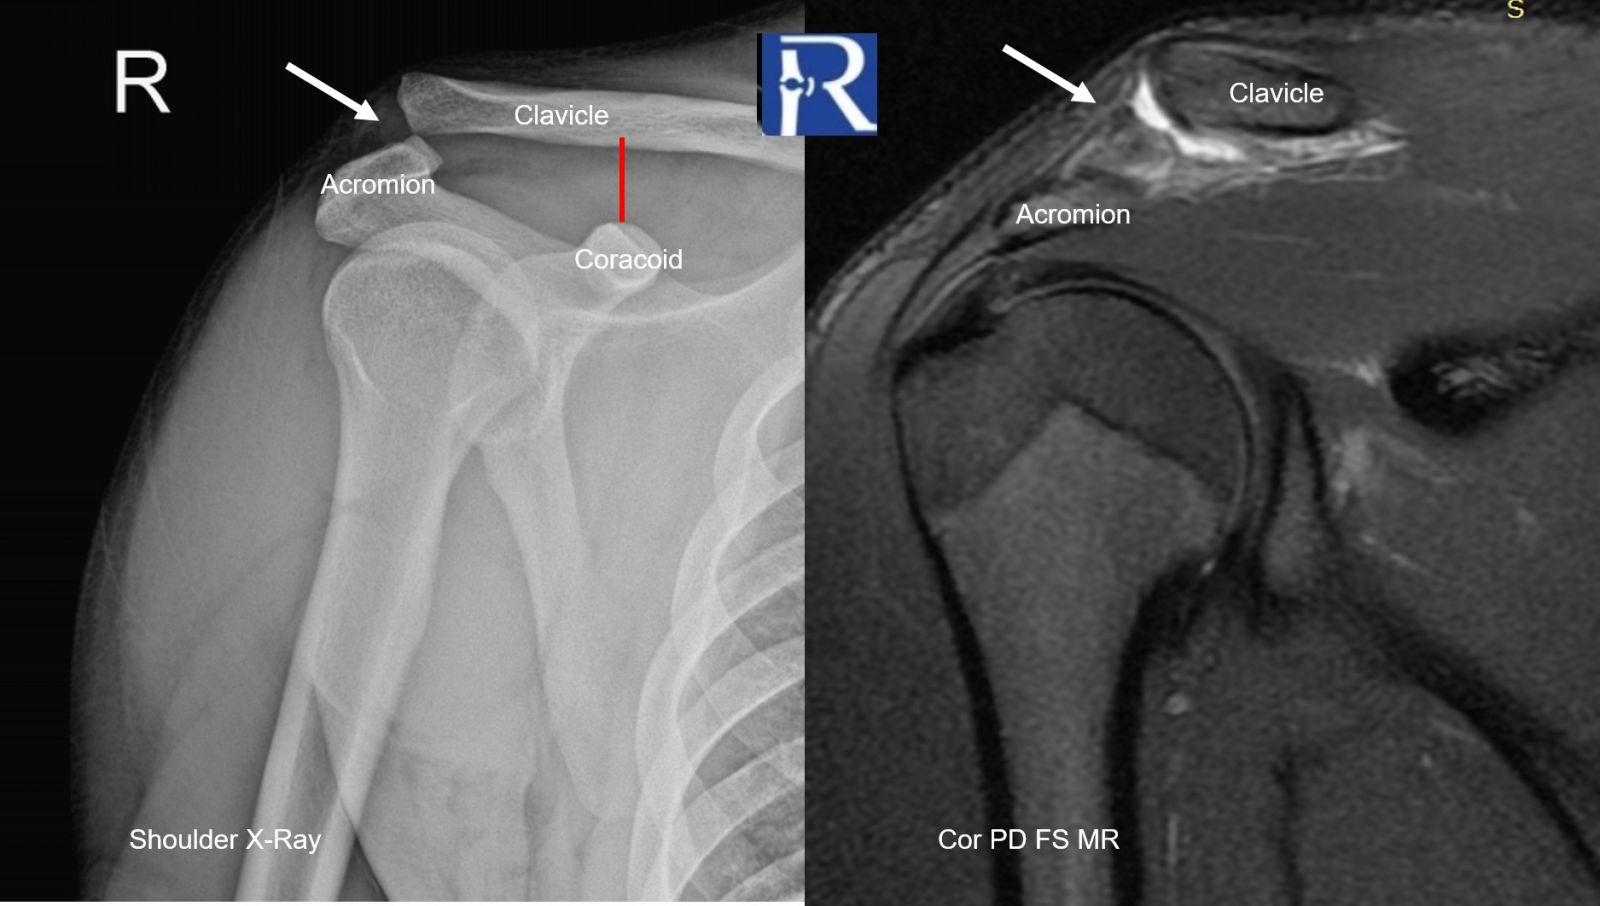

Plain Radiography (AP Shoulder)

- Superior displacement of the clavicle relative to the acromion (white arrow)

- Inferior cortical margin of the clavicle overriding the superior cortex of the acromion (white arrow)

- Increased coracoclavicular (CC) distance measuring approximately 20 mm (red line)

→ Findings are consistent with acromioclavicular joint separation

Magnetic Resonance Imaging (MRI)

- Full-thickness tear of the acromioclavicular ligament (white arrow)

- Fluid/hemorrhagic signal within the AC joint (white arrow)

- Persistent widening of the coracoclavicular distance (~20 mm) (red line)

→ MRI confirms complete ligamentous disruption consistent with Grade 3 injury